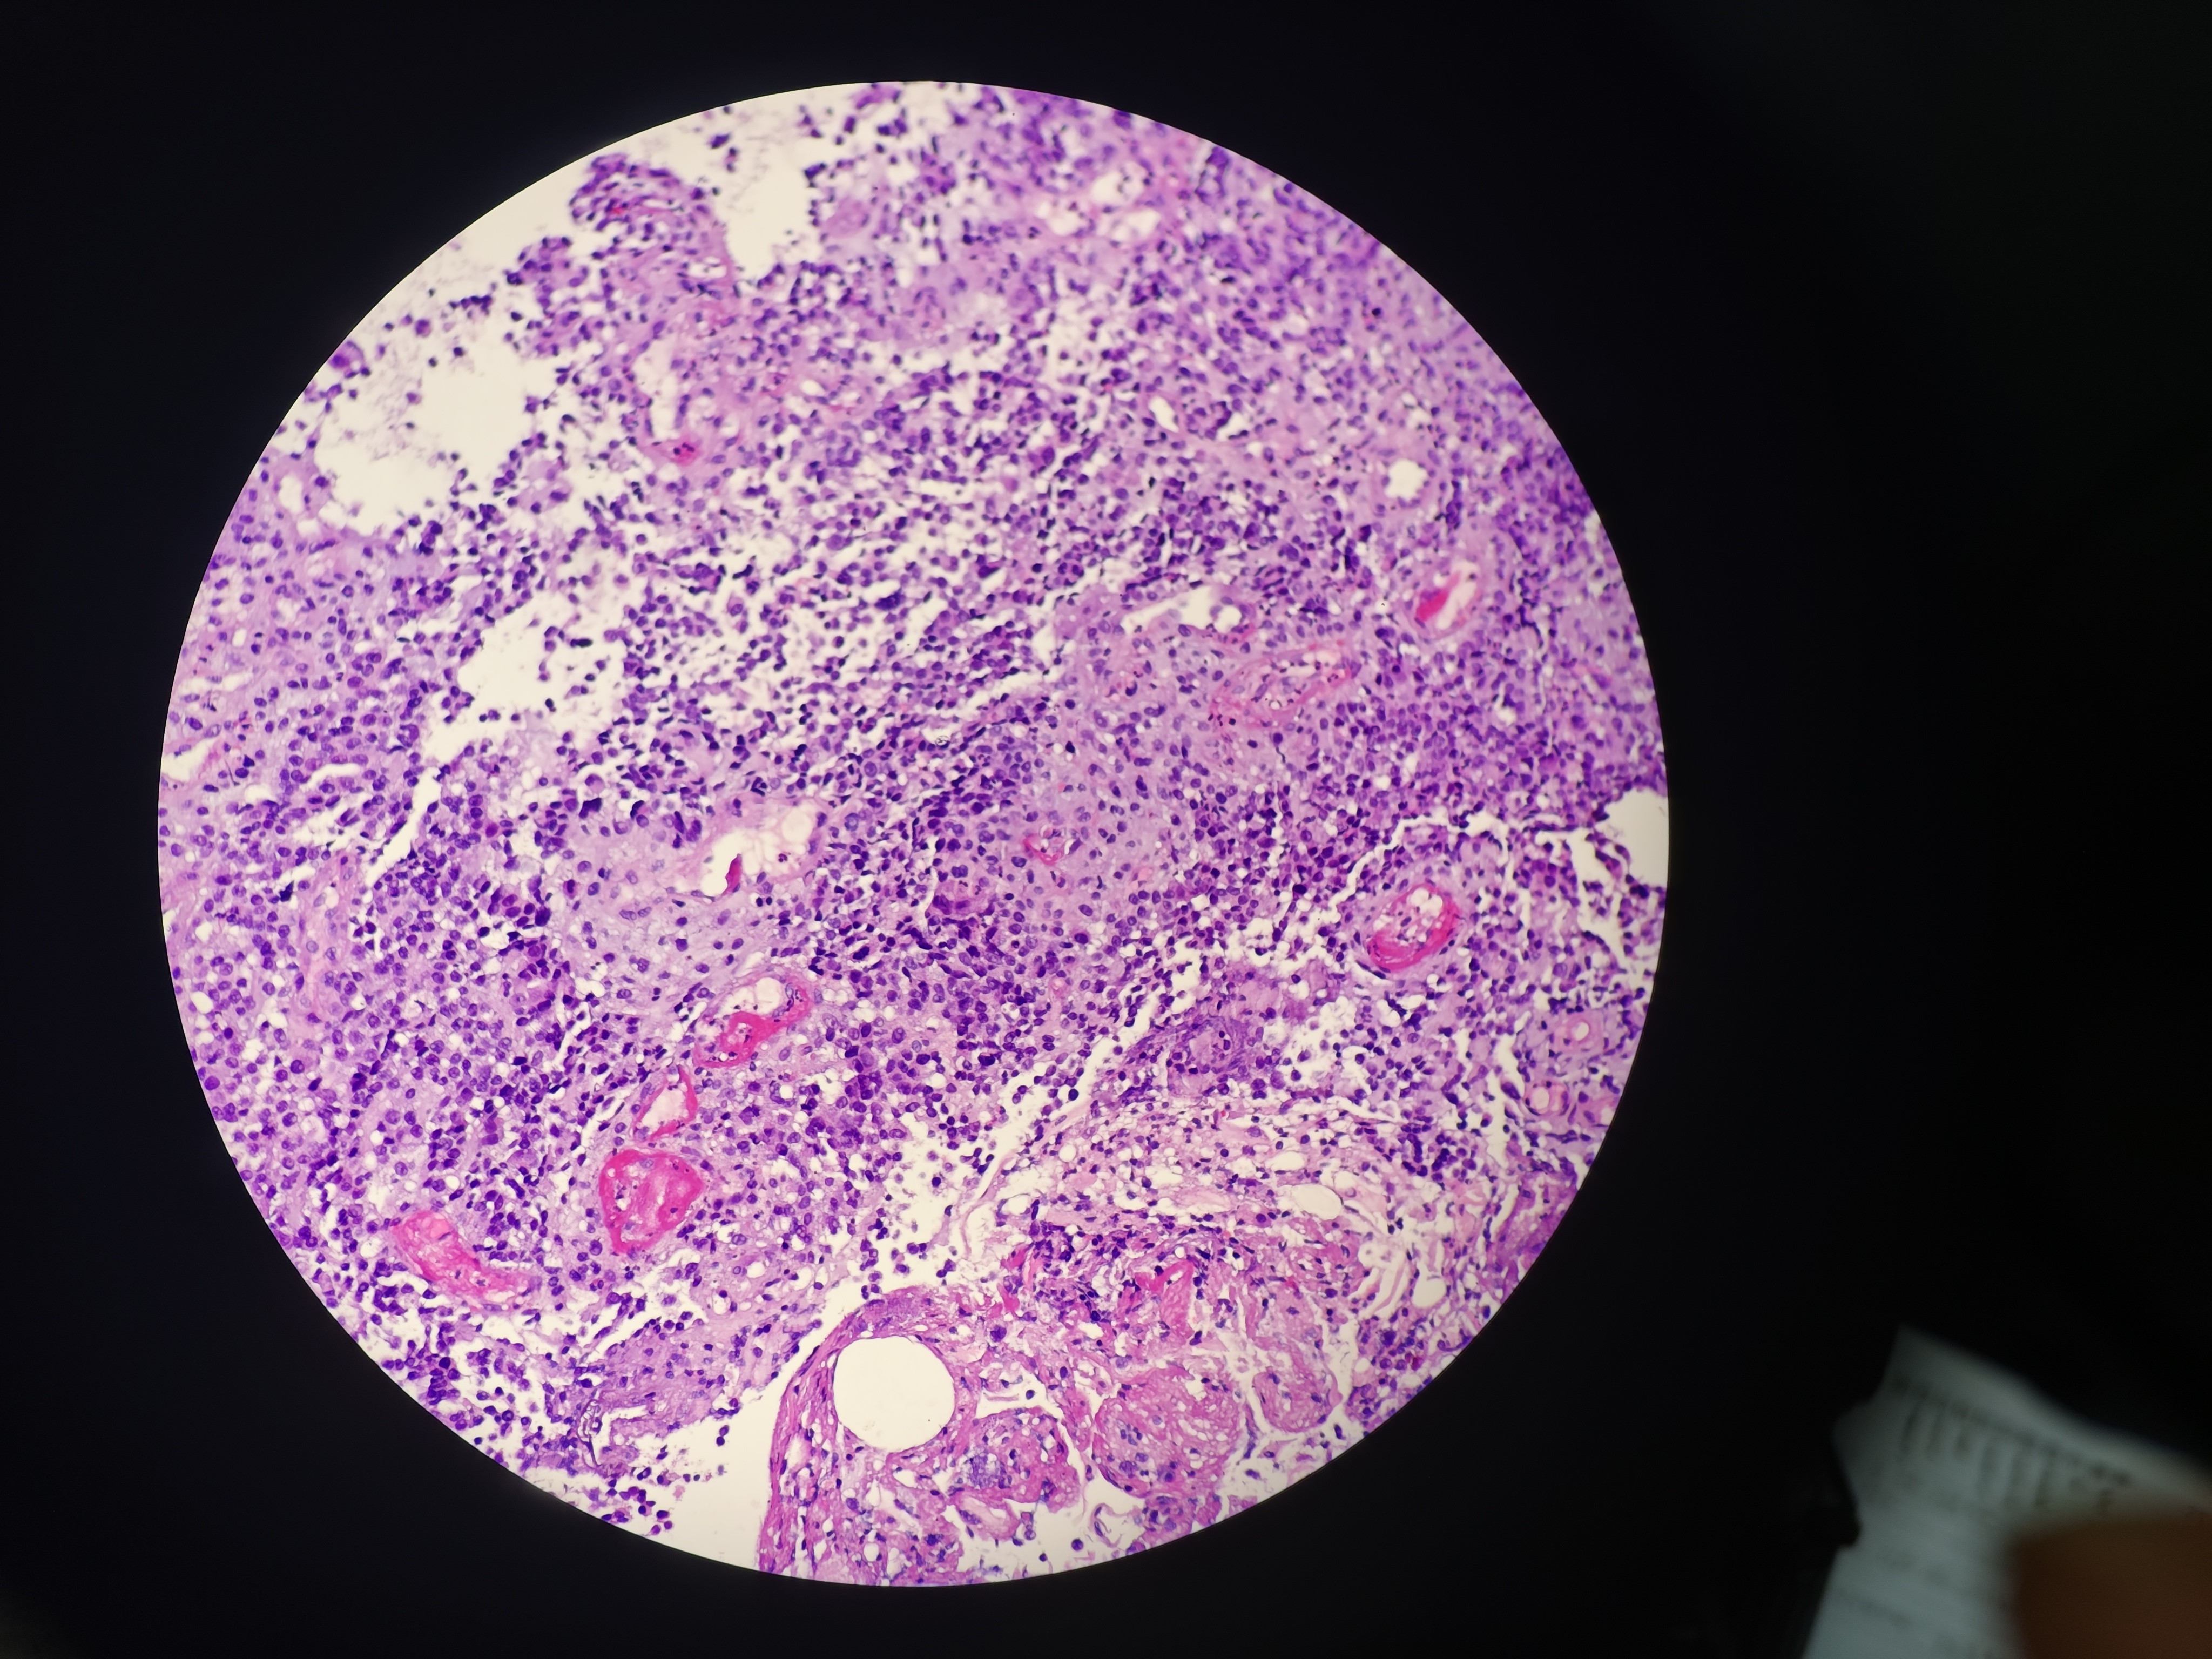

食管癌

食管距门齿33~38cm处可见环管腔半周隆起性病变,表面破溃,易出血,活检6块,质脆

食管活检

灰白软组织6块,直径0.1~0.2cm

请教老师,这个报什么癌?